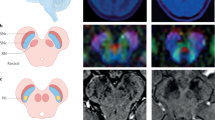

Adult rats received a single unilateral stereotaxic injection of an adeno-associated viral (AAV) vector expressing human tyrosinase (hTyr) above the right SNpc (Fig. 1a). By 2–4 weeks (w) post-AAV-hTyr injection, up to ~80–90% of ipsilateral SNpc DA neurons were transduced and expressed the hTyr protein (Fig. 1b). By 2 months (m) post-AAV-hTyr injection, the ipsilateral SNpc from these animals could be visualized macroscopically, in the absence of any staining, as a darkened brown area, similar to human melanized SNpc tissue (Fig. 1c). In contrast, the contralateral SNpc from the same animals could not be detected macroscopically, as rodents lack NM (Fig. 1c). Similar to humans, ipsilateral SNpc from AAV-hTyr-injected animals could also be detected macroscopically as a hyperintense area by NM-sensitive high-resolution T1-weighted magnetic resonance imaging (Fig. 1d). Optical microscopy visualization confirmed that the darkened SNpc area in AAV-hTyr-injected rats corresponded to the presence of an intracellular dark-brown fine granular pigment analogous to human NM within ipsilateral SNpc neurons (Fig. 1e). Virtually all (~97%) hTyr-expressing SNpc DA neurons from AAV-hTyr-injected animals produced NM (Supplementary Figure 2). As in humans, NM from AAV-hTyr-injected rats stained prominently with the melanin marker Masson-Fontana, which reflects the ability of NM to chelate metals (Fig. 1f). Ultrastructural examination by electron microscopy identified NM granules from AAV-hTyr-injected rats as membrane-delimited autophagic structures with an electron-dense matrix of irregular shape and size, associated with characteristic lipid droplets, equivalent to what has been described in humans23 (Fig. 1g). Within the SNpc, NM pigment in AAV-hTyr-injected rats was restricted to TH−immunopositive DA neurons (Supplementary Figure 2), thereby mimicking the pattern of human NM distribution within catecholamine-producing neurons6.

Human-like NM production in AAV-hTyr-injected rats. a Schematic representation of the site of AAV-hTyr unilateral stereotaxic injection above the SNpc of the rat brain. b Representative photomicrographs of a 30-μm-thick ipsilateral SNpc section from an AAV-hTyr-injected rat (1 m post-AAV injection) immunostained for TH (red) and hTyr (green). Scale bar, 500 μm. c Left, representative unstained AAV-hTyr-injected rat brain (2 m post-AAV injection) mounted in a cryostat in which ipsilateral SNpc can be detected macroscopically as a brown, darkened area (dashed outline). A hole was made in the contralateral hemisphere as anatomical reference. Right, representative unstained midbrain from a 62-year-old human control subject (Hu) in which the SNpc can be detected macroscopically (bilateral dashed outlines). d Representative NM-sensitive high-resolution T1-weighted magnetic resonance imaging of an AAV-hTyr-injected rat brain at 2 m post-AAV injection (left, ex-vivo) and of a 59-year-old human control brain (Hu, right, in vivo). SNpc can be detected as a unilateral (AAV-hTyr-injected rodent) or bilateral (human) hyperintense area (dashed outlines). e Representative photomicrograph of an unstained 30-μm-thick ipsilateral SNpc section from an AAV-hTyr-injected rat (2 m post-AAV injection) in which NM is shown in brown. Inset, high magnification of a melanized neuron. Scale bars, 100 μm and 12.5 μm (inset). f Representative photomicrographs of Masson-Fontana melanin staining (NM in dark brown) in 5-μm-thick SNpc sections from an AAV-hTyr-injected rat at 2 m post-AAV injection (left) and an 80-year-old human control subject (Hu, right). Scale bars, 25 μm (left) and 12.5 μm (right). g Representative electron micrograph of NM granules in the ipsilateral SNpc of an AAV-hTyr-injected rat at 4 m post-AAV injection (left) and a 75-year-old human control subject (Hu, right). NM pigment is detected as an electron dense matrix. Characteristic associated lipid droplets are indicated with asterisks. Scale bars, 500 nm